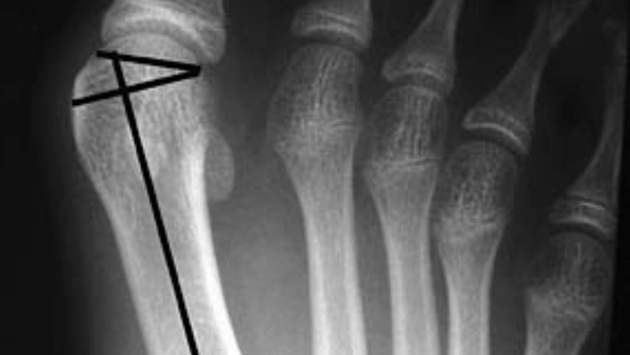

Но повлиять на появление вальгусной деформации стопы могут травмы, особенно у спортсменов. Это может привести к разрывам сухожилий и травмам костей. Этот фактор — предпосылка к образованию шишки в месте перелома плюсневой кости.

А способ избавиться от шишки на ноге один — операция. Только так можно выздороветь и избавиться от боли.

«Если вы думаете, что про шишку на ноге можно просто забыть, достаточно поносить некоторое время ортопедические стельки, то глубоко заблуждаетесь. Последствия вальгусной деформации могут быть крайне неприятными. Прежде всего, это резкая боль при ходьбе и, как результат, стеснение движений. Согласитесь, никто в такой ситуации не готов это постоянно терпеть. Поэтому я как врач вижу единственный выход — в хирургическом удалении шишки», — подчеркнул специалист.